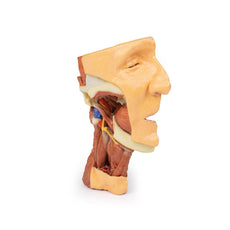

The neck: The musculoskeletal portion of the neck have been removed to display the pharynx posteriorly, the larynx anteriorly, and the neurovascular bundles laterally. The suprahyoid and infrahyoid muscles can be seen on the neck, as well as the cricothyroid muscle.

When looking up the length of the trachea from below, the vocal folds are visible. The hypoglossal nerve can be seen winding around the lateral surface of the external carotid artery and the external branch of superior laryngeal nerve is seen descending in the neck. The internal jugular vein, the common carotid artery and its bifurcation into external and internal carotid arteries are clearly seen on both left and right. The vagus nerve in the carotid sheath is also visible. The ansa cervicalis is visible emerging below the digastric muscle and descending on the surface of the internal jugular vein. The internal branch of the superior laryngeal nerve can be seen below the superior thyroid artery on the left. The superior thyroid artery branching from the external carotid artery is seen descending in the anterior neck. The internal branch of the superior laryngeal artery is visible on the left piercing the thyrohyoid membrane above the inferior constrictor where this muscle is attached to the hyoid bone.

The neck: The musculoskeletal portion of the neck have been removed to display the pharynx posteriorly, the larynx anteriorly, and the neurovascular bundles laterally. The suprahyoid and infrahyoid muscles can be seen on the neck, as well as the cricothyroid muscle.

When looking up the length of the trachea from below, the vocal folds are visible. The hypoglossal nerve can be seen winding around the lateral surface of the external carotid artery and the external branch of superior laryngeal nerve is seen descending in the neck. The internal jugular vein, the common carotid artery and its bifurcation into external and internal carotid arteries are clearly seen on both left and right. The vagus nerve in the carotid sheath is also visible. The ansa cervicalis is visible emerging below the digastric muscle and descending on the surface of the internal jugular vein. The internal branch of the superior laryngeal nerve can be seen below the superior thyroid artery on the left. The superior thyroid artery branching from the external carotid artery is seen descending in the anterior neck. The internal branch of the superior laryngeal artery is visible on the left piercing the thyrohyoid membrane above the inferior constrictor where this muscle is attached to the hyoid bone.